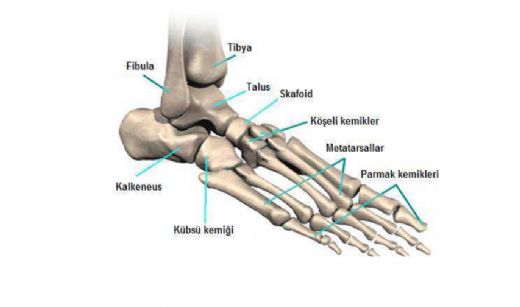

Ayak Bileği Çatlağı Nedir?

Ayak bileği çatlağı, ayak bileğindeki kemiklerin (genellikle tibia, fibula veya tarsal kemikler) bütünlüğünün bozulmasıyla oluşan bir yaralanmadır. Bu tür yaralanmalar, çeşitli derecelerde olabilir ve genellikle aşağıdaki belirtilerle kendini gösterir:

• Ağrı

• Şişlik

• Morarma

• Hareket kısıtlılığı